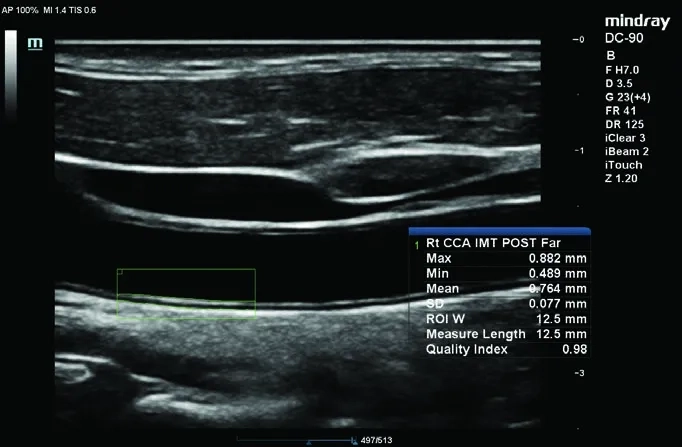

• Smart 3D — ПО для построения 3D-изображений с использованием 2D-датчиков;

• Natural Touch Elastography — ПО для оценки эластичности тканей методом компрессионной эластографии;

• iScape™ View — модуль панорамного сканирования.